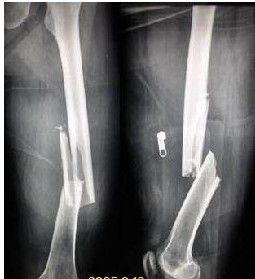

股骨头骨折多因软强的间接暴力所致,可以单独发生,但更多的是合并于髋关节脱位。髋关节前脱位可合并股骨头上方的骨折,髋关节后脱位,可并发股骨头内下方的骨折或头上部的骨折,有时也可见到股骨头粉碎骨折。